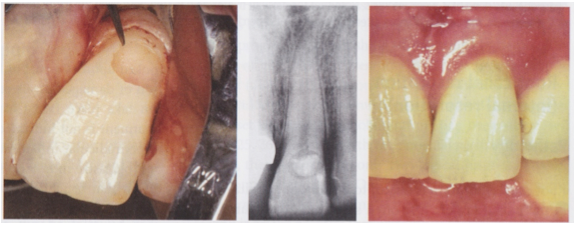

Case 4– #14 ECIR Class III with external surgical repair

48 y/o female presented complaining of a food trap on the palatal surface of #14. She was not experiencing any discomfort. Clinical exam revealed a circular ECIR lesion of about 5mm in diameter on the L surface of #14, extending 1mm subgingivally. The tooth tested WNL to cold was the pulp was vital. Radiographic exam revealed the lesion was superimposed over the pulp chamber and mostly within the cervical 1/3rd of the clinical crown. Apical tissues were WNL and there was no evidence of periapical pathology. Because the lesion is mostly supragingival secondary decay was noted and excavation resulted in a pulpal exposure.

Endodontic treatment was completed. The coronal 3mm of the P canal was filled with Geristore in preparation for the ECIR repair. Palatal tissue was reflected to gain full access to the defect. All decay and resorptive tissue was removed mechanically and I soaked the prep with 90% TCA. Geristore was placed as a restoration and the flap was re-approximated and sutured into place. The patient was referred to her general dentist for the crown. Recall not yet available.